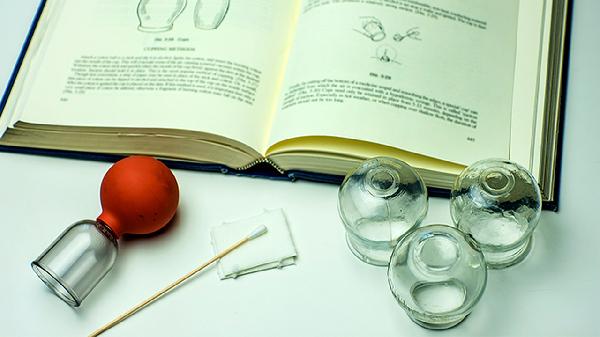

拔罐的禁忌和注意事项

拔罐疗法需避开皮肤破损、出血倾向、严重疾病急性期等禁忌情况,操作时需注意罐具消毒、留罐时间、体位选择等关键事项。1、禁忌人群:皮肤溃疡、湿疹等皮损患者禁用拔罐,避免感染扩散;血友病、血小板减少等出血性疾病患者可能引发皮下出血;妊娠期妇女腰腹部慎用,以免刺激子宫;高热抽搐、心肾功能衰竭等急重症患者禁用。恶性肿瘤局部、骨折未愈合部位同样禁止施术。2、禁忌部位:颈...

拔罐的禁忌 拔罐的原理和禁忌

拔罐疗法通过负压吸附刺激经络穴位,但存在皮肤破损、出血倾向、严重慢性病等禁忌。主要禁忌包括皮肤感染、凝血功能障碍、妊娠期腰腹部操作、空腹或饱食后立即操作、体质极度虚弱五类情况。1、皮肤感染:局部存在疱疹、溃疡、烧伤等皮肤损伤时禁止拔罐。罐体负压可能加重创面渗出,导致继发感染扩散。皮肤屏障功能受损区域操作易引发接触性皮炎,愈合期患者需待表皮完全修复后再考虑拔罐...

拔罐的禁忌 拔罐不适合哪些人

拔罐疗法并非人人适用,皮肤破损者、血液疾病患者、孕妇腰腹部、严重心脏病患者及体质极度虚弱者均属禁忌人群。拔罐禁忌主要涉及皮肤状态异常、凝血功能障碍、特殊生理阶段、心血管风险及体质因素五类情况。1、皮肤破损:局部存在伤口、湿疹、疱疹或烧伤时,负压刺激可能加重皮肤损伤,导致感染扩散。糖尿病患者皮肤愈合能力差,即使微小破损也应避免拔罐。皮肤过敏急性发作期同样不适宜...

拔罐的坏处与注意事项

拔罐疗法可能引起皮肤淤血、水泡、感染等不良反应,操作时需注意体质禁忌与部位选择。主要风险包括局部淤血、皮肤损伤、晕罐反应、感染风险及加重特殊病情,需严格遵循操作规范并避开禁忌人群。1、局部淤血:拔罐形成的负压会导致毛细血管破裂,出现紫红色罐印属于正常现象。但留罐时间过长或负压过大时,可能造成深层组织淤血,表现为皮肤青紫面积扩大且消退缓慢。气血虚弱者更易出现此...